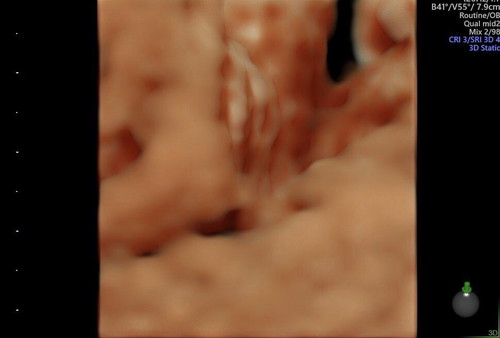

Hai saja nk share haritu buat scan phtu doc ckp girl kalau 3 line mcm ni ?. Ibu2 yg dh dpt bby girl betoi x ? Share2 la. Due hujung bulan 7.. masa scan ni 28weeks. Ni Anak kedua. Ank sulung boy..?

Insha Allah girl ni sis.. sy dlu pon scan swasta doc ckp 3 line ni girl, scan kk pon sama jgk.. alhamdulillah, bersalin bln 2 hritu mmg bby girl Allah bagi..😊anak sulung sy boy..😉

Masa saya scan pon dokter tunjuk ada 3 garisan jugak. Dr dokter swasta and dokter kk cakap yg sama. Hope aamiin

Tahniah baby girl,saya pon scan nmpk bentuk mcmtu mmg keluar girl..skrg dh 38hr berpantang 😃😃